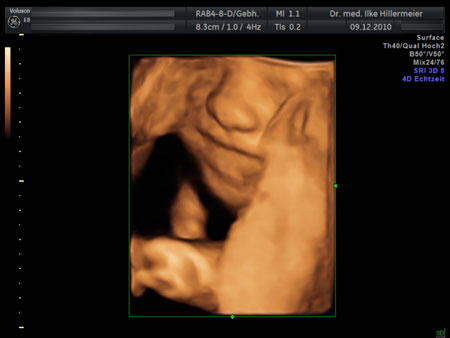

Ultraschalluntersuchungen in der Schwangerschaft

27. Schwangerschaftswoche

27. Woche